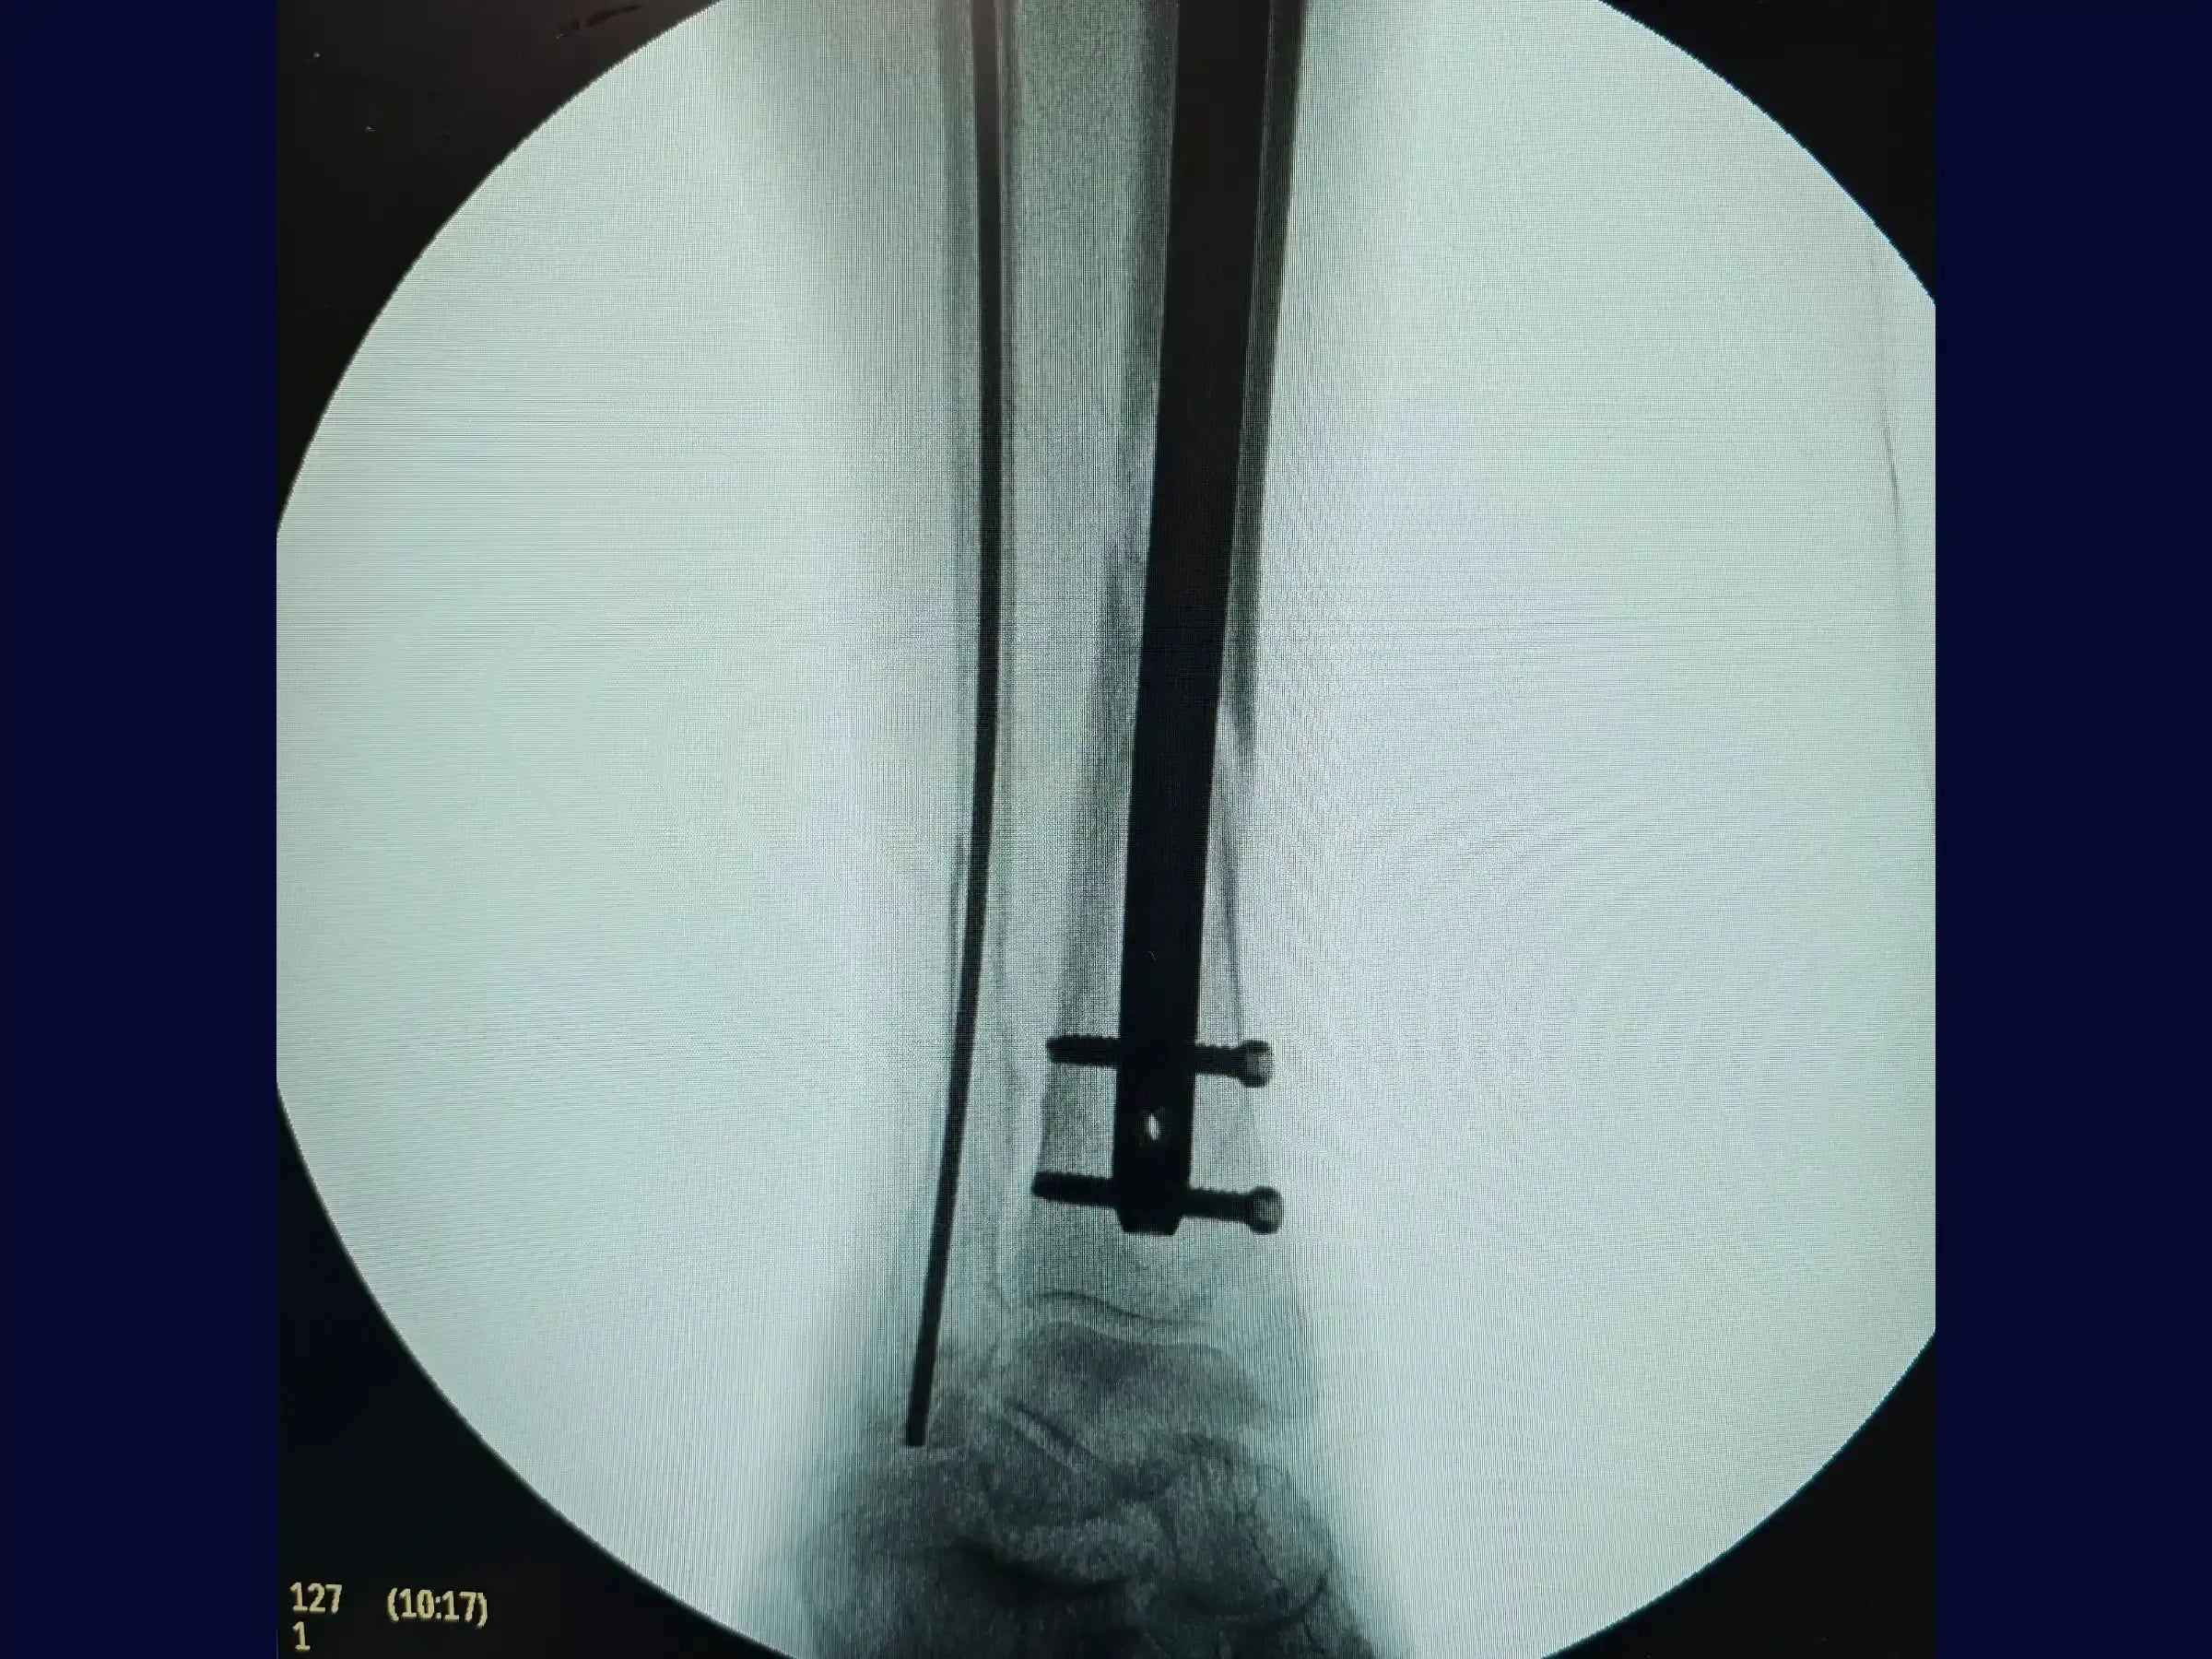

- Bloqueio Proximal e Distal: Execução do bloqueio proximal percutaneamente com o paciente mantendo a perna em posição estável, e técnica de "mão livre" para os parafusos de bloqueio distal, com marcação precisa da pele para evitar atrito com partes moles.